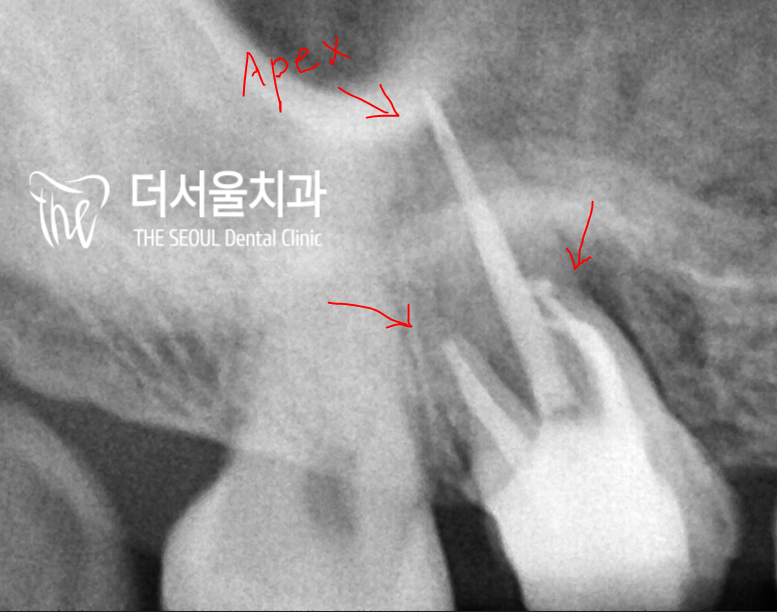

드디어 리엔도 과정이 끝났는데요.

뿌리 끝까지 확실하게 채워져 있었으며

크라운도 예쁜 모양으로 잘 만들어져 있네요.

색도 자연치와 유사하고

어금니 특유의 해부학적 형태 또한

재현이 잘 되어 있었습니다.